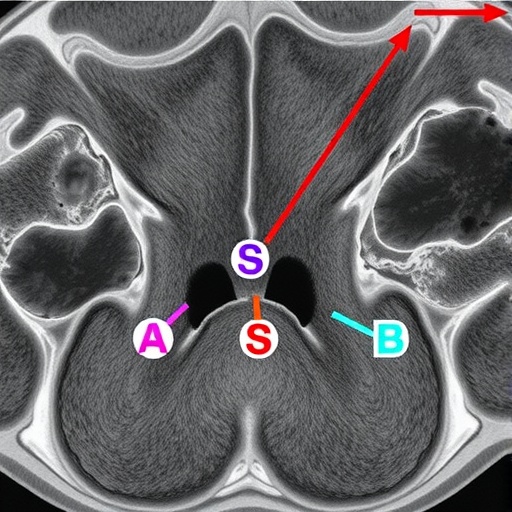

Interestingly, the researchers observed that meningiomas with FOS/FOSB gene fusions tend to occur in specific anatomical locations within the central nervous system, suggesting that microenvironmental factors may influence the selective advantage conferred by these rearrangements. This spatial predilection reinforces the notion that tumor microenvironment and intrinsic genetic alterations jointly shape meningioma pathogenesis.